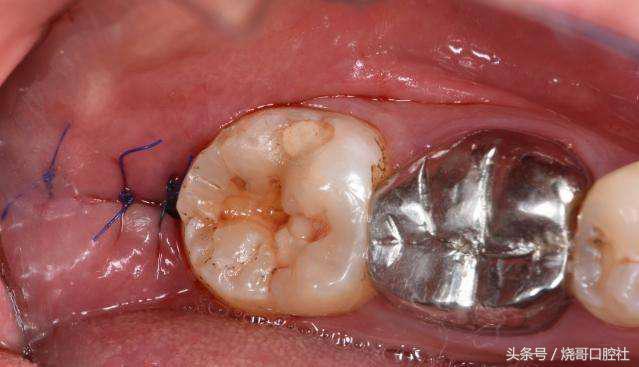

拔牙后是可以不用拆线的!比如羊肠线可以免拆,自动被牙龈组织吸收,但普通缝合线不可吸收,一般在5~7天内进行拆线处理,如果不及时拆线,要注意缝合线和牙龈长在一起,细菌会刺激牙龈发炎红肿,甚至引起口腔溃疡。

关于缝不缝线具体得看创口大小,术后较大创口都需要缝线,这样才能止血预防感染,而创口小的直接不用处理,靠血凝块自主保护,所以千万不要去破坏它,也不能吐口水。

1、食物残渣会更容易聚集在缝合线上,细菌在线周围组织滋生,感染牙龈后炎症是一回事,关键牙槽骨逐渐吸收,这才是最可怕的,因为牙龈也会跟着萎缩。